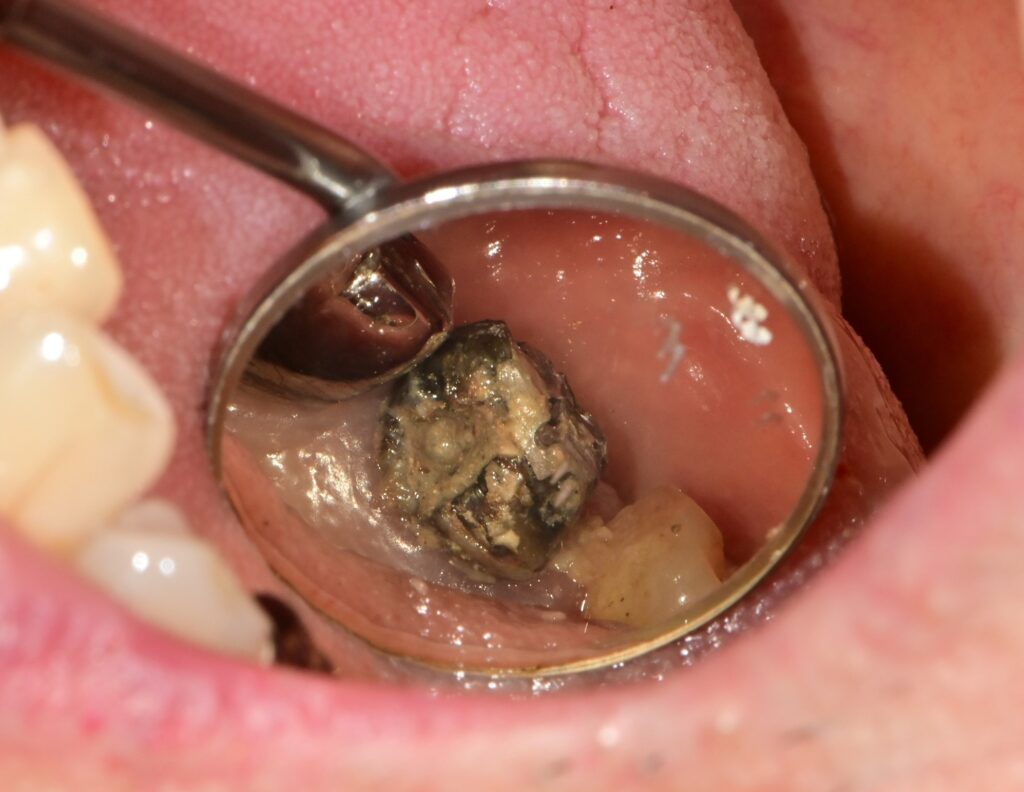

하치조신경 전달마취 하에 #37 난발치를 시행하였습니다.

치아는 골 유착으로 인해 단순 발치가 어려워 BURR를 이용한 치근 분할 후 발치를 진행하였으며,

발치 후 봉합(suture)까지 시행하였습니다.